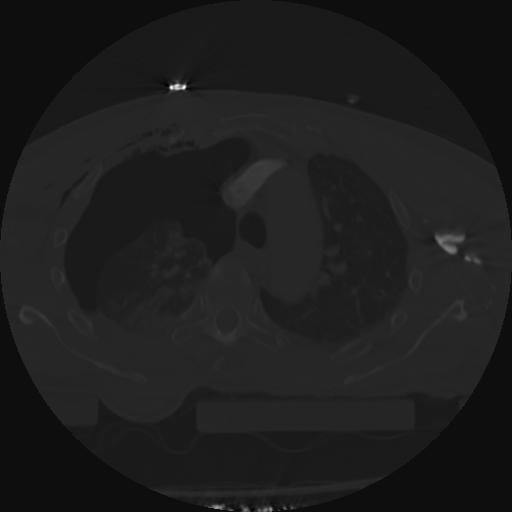

22 ANGIO,CE,Vol,0.5,ANGIO,,